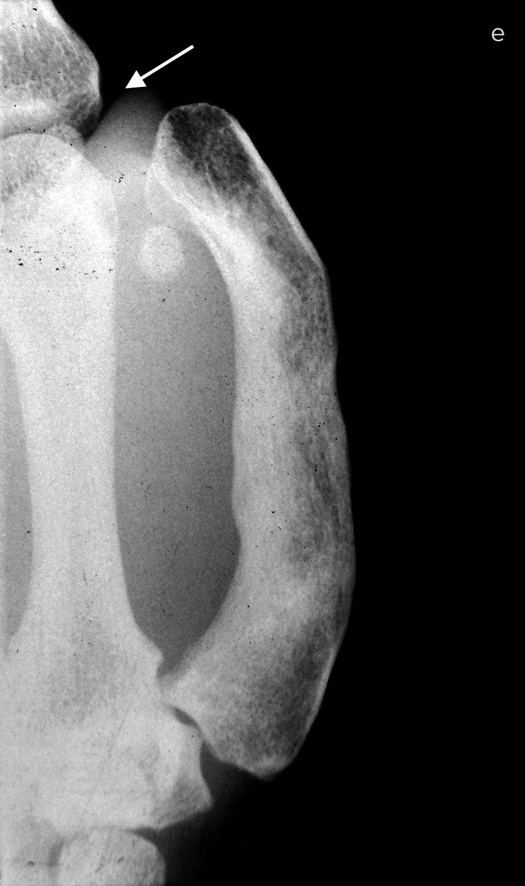

Бывает, что на одной кисти руки не хватает сразу нескольких пальцев или пациенту нужны все пальцы. В этих случаях «пригласить соседа» не получится. Если не удается «уговорить» культю вырасти, хирург может прибегнуть к «краже». Жертвой становится стопа. Большие пальцы ноги по форме почти идентичны своим собратьям на руках, поэтому именно они чаще всего идут в дело — вот только место преступления выглядит довольно неприглядно.

Если похитить второй палец ноги, замена из него получится совсем тощая, зато ступня будет иметь аккуратные очертания. Такой вариант обычно выбирают в странах, где в помещении принято снимать обувь. На способность ходить и бегать отсутствие первого или второго пальца ноги почти не влияет.

Операция по пересадке пальца с ноги на руку длится от пяти до десяти часов и требует прекрасного владения навыками микрохирургии. Хирург определяет нервы, артерии, вены и сухожилия пальца стопы, изолирует их и отрезает вместе с костью. Ампутированный палец переносят на руку и стыкуют аналогичные ткани между собой. Хирург обычно крепит кость пересаженного пальца к оставшейся в руке кости с помощью стальных штырей.

Диаметр кровеносных сосудов — от полутора до трех миллиметров: их необходимо точно соединить практически невидимыми швами, ведь кровь должна двигаться по сосудам, не просачиваясь наружу. Когда кровообращение возобновится, концы кости будут спокойно заживать, не понимая, что стопа перепуталась с кистью руки. Пройдут месяцы, в пересаженный палец врастут новые нервные волокна, и чувствительность восстановится. По-английски получившуюся комбинацию иногда называют thoe.